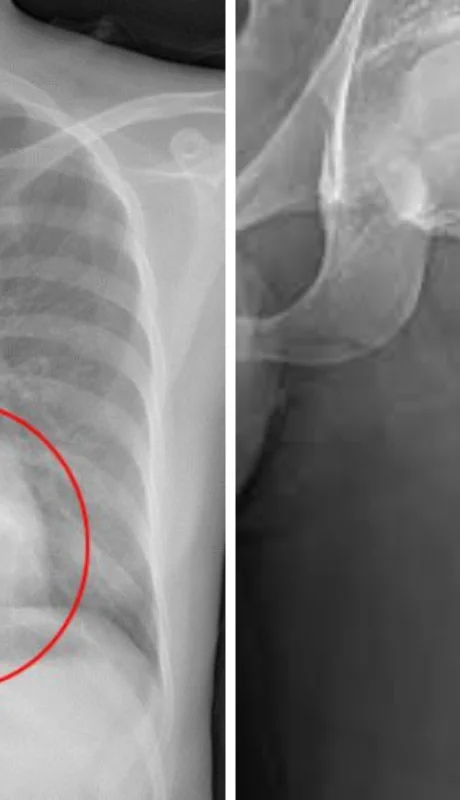

Osteoblastoma: síntomas, estudios y tratamiento recomendado